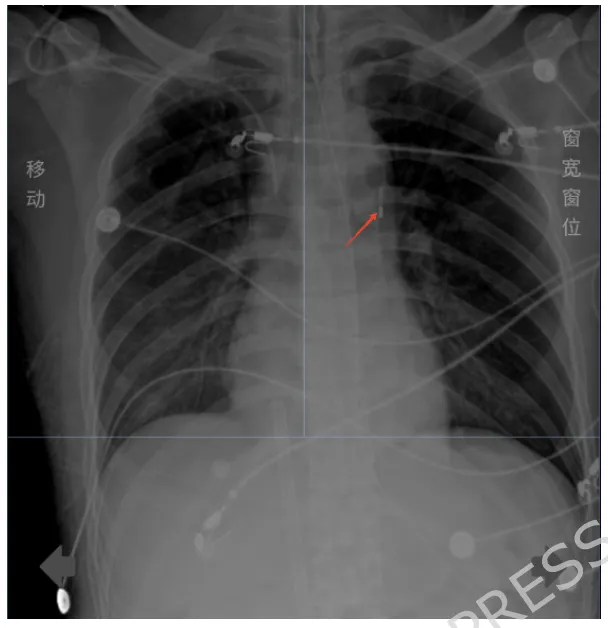

2025年1月,一名36岁男性因“发热5天、胸闷胸痛2天”被送入急诊。他没有心脏病史,却在短短数日内由一场“感冒”迅速演变为危及生命的爆发性心肌炎。急诊心电图提示窦性心动过速、左前分支阻滞、低电压;肌钙蛋白I 3.320 ng/mL、肌钙蛋白T 0.939 ng/mL,明确指向急性心肌损伤。尽管初期生命体征尚平稳,但在转运至心脏ICU途中,患者突发心脏骤停,经心肺复苏后恢复自主循环,但仍处于严重心源性休克状态,依赖大剂量血管活性药物维持。这正符合2021年国际心肌炎共识中提出的“红色警报”特征——青年男性、流感样前驱症状、肌钙蛋白显著升高,提示病情可能急剧恶化。

此时,床旁心脏超声显示全心收缩弥漫性减弱、心输出量极低,SCAI休克分期已进展至C期。心肌炎症导致的“电风暴”使心脏处于极度不稳定状态,随时可能再次停搏。临床团队面临的关键问题是:在如此危急的情况下,应选择何种机械循环支持策略,才能为心肌修复争取时间